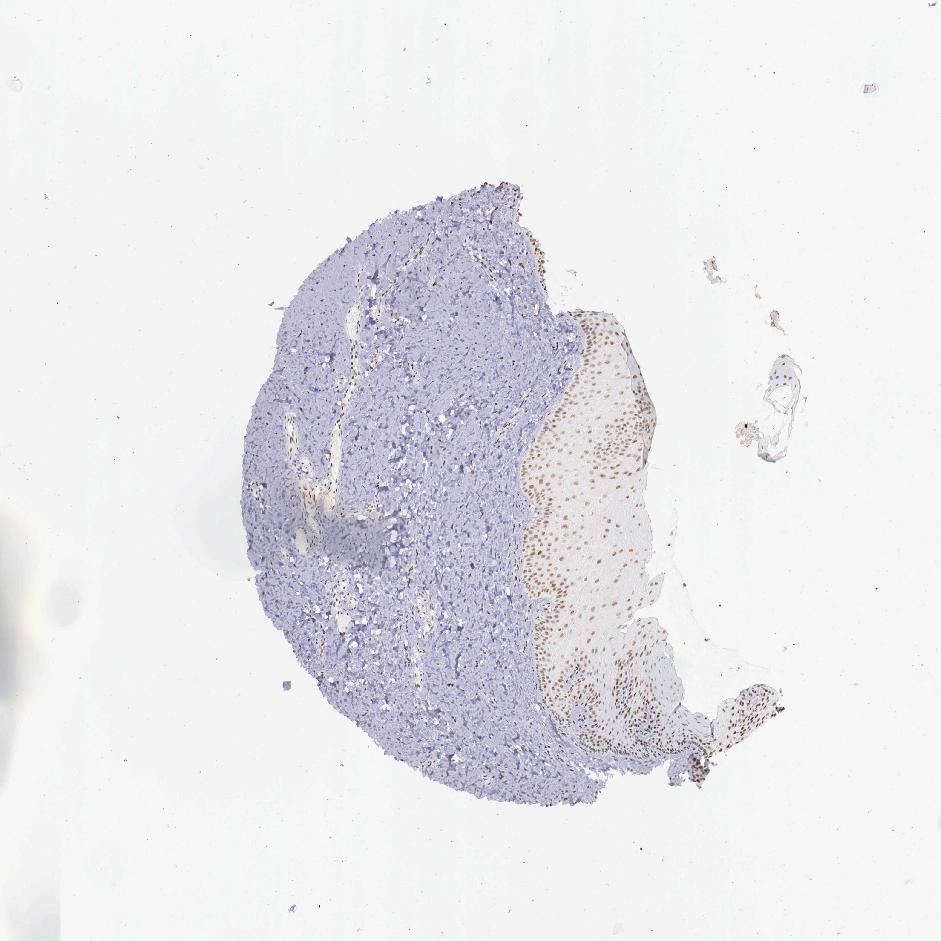

TISSUE PRIMARY DATA ORAL MUCOSA Show tissue menu

ORAL MUCOSA - Antibody stainingi

Antibody staining in the annotated cell types in the current human tissue is reported as not detected, low, medium, or high, based on conventional immunohistochemistry profiling in selected tissues. This score is based on the combination of the staining intensity and fraction of stained cells.

Each image is clickable and will lead to virtual microscopy that enables deeper exploration of all samples and also displays staining intensity scores, fraction scores and subcellular localization as well as patient and tissue information for each sample.

Antibody HPA001853Antibody HPA012292Antibody CAB000330

Squamous epithelial cells MediumLowLow